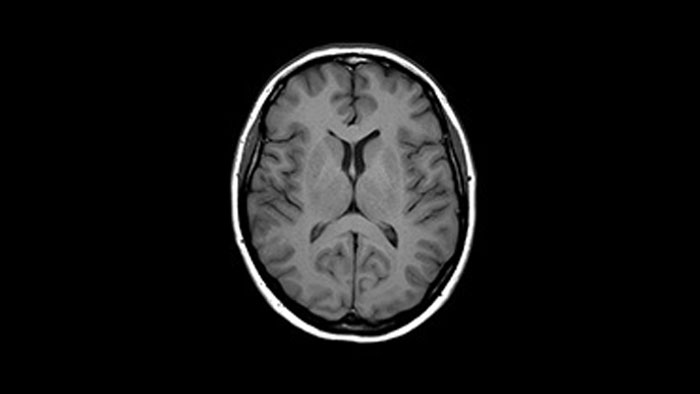

Enhanced diagnostic confidence in neuro oncology

Find the right clinical applications for your needs